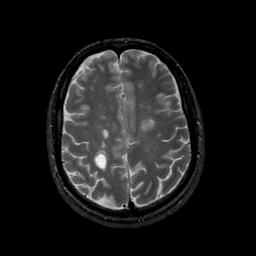

MR Study #11, May 5, 1991 -- Slice #36